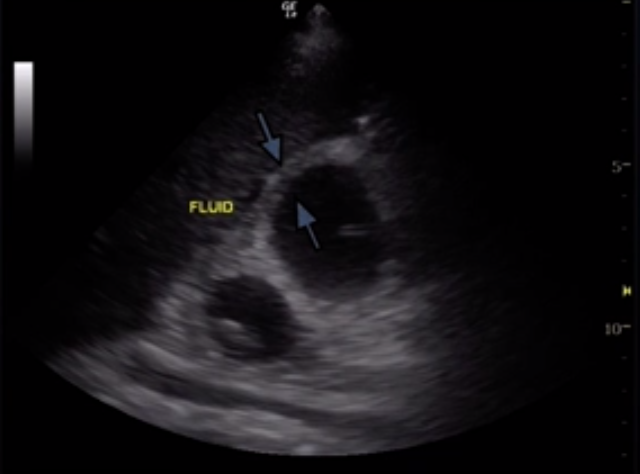

The gallbladder wall should typically be < 3 mm but some may use 3.5 mm as a cutoff for normal. It is important to always use the anterior wall to measure thickness as this is not obscured by bowel gas. You also should be assessing for pericholecystic fluid around the gallbladder wall which will appear as a thin hypoechoic stripe.

• Be careful when you are assessing the gallbladder wall which appears poorly delineated as this may suggest significant wall edema and false measurement can lead to missed diagnosis of cholecystitis (as seen above).

• Pericholecystic fluid is not that helpful (similar to a coin flip) but if seen it may push you towards your diagnosis of cholecystitis